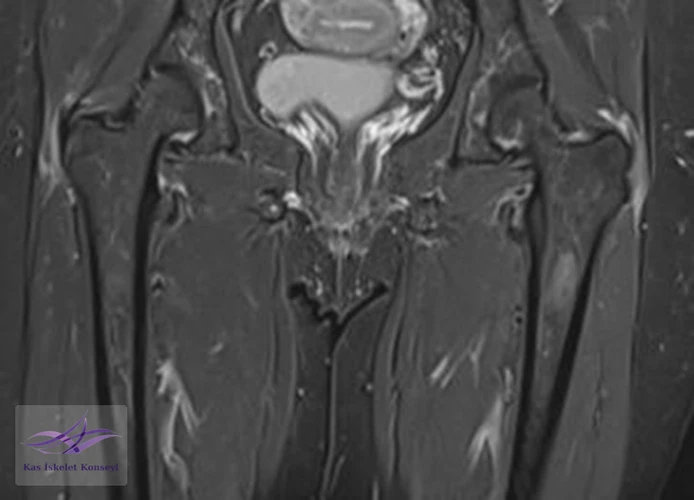

İncelemeler: Lomber MRG: L4-5 diskal bulging ve sol foraminal stenoz var. Kalça MRG istendi, iki yanlı trokanterik bursit rapor edildi.

Resim 4. Kalça MRG koronal kesit, solda hakim iki yanlı trokanterik bursit ile uyumlu.

Resim 5. Kalça MRG, aksiyal kesit.

Tedavi için öncelikle trokanterik bursa enjeksiyonları öngörüldü. Bu tedaviden alınacak yanıt görüldükten sonra mevcut lomber patolojisinin (foraminal stenoz) tekrar değerlendirilmesi önerildi. İki yanlı belirgin trokanterik bursit görülmesi nedeniyle polimyalgia romatika açısından da incelenmesi önerildi.